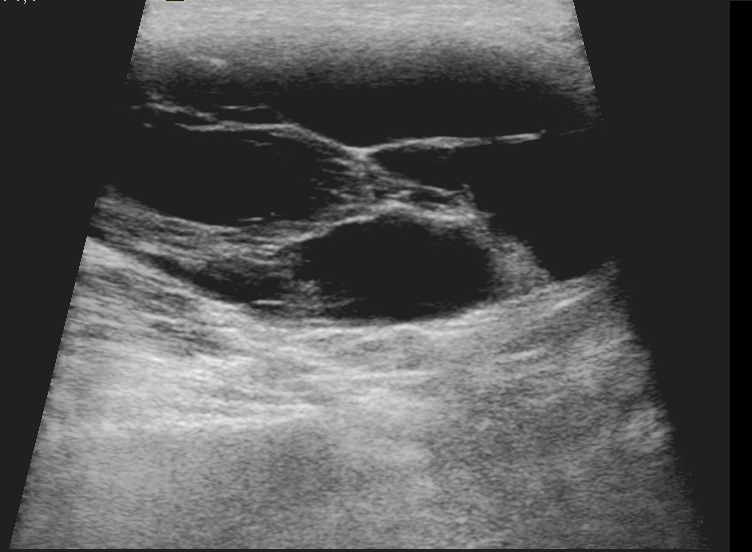

US – an ideal tool for the examination of neck soft tissue - can be first-line modality in case of palpable neck mass, thyroid enlargement, dysphagia and persistent hoarseness. US is widely available and capable of multiplanar, real-time visualization. US can determine whether a mass is cystic or solid and therefore able to differentiate between adenitis, cellulitis and abscess. One of the most frequent cystic neck mass is the branchial cleft cyst , which arises on the lateral part of the neck from a failure of obliteration of the second branchial cleft in embryonic development. Most common palpable neck mass in adults is related to metastatic lymphadenopathy, which is the early sign of pharyngeal or laryngeal carcinoma in many cases. A round, enlarged (> 10 mm) lymph node with loss of internal structure suggests malignancy. Enlarged lymph nodes in children are caused by lymphadenitis most frequently; however, in this case the central hilus remains echogenic and the internal structure is normal.

4. image: Young male patient with a left supraclavicular lump. Upper panel: complex cystic mass with sepatations; normal flow in the neighbouring vessels. Lower panel: T2W, postcontrast T1W, fat-saturation T1W MRI suggest cystic lymphangioma (Asklepios Klinik Altona, Hamburg)